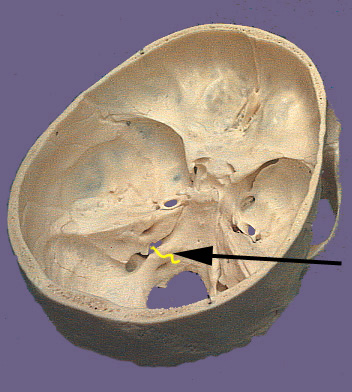

Cranium CN X

CN X. Vagus Nerve.

The vagus nerve is the longest of the cranial nerve. Its name is derived from Latin meaning "wandering". True to its name the vagus nerve wanders from the brain stem through organs in the neck, thorax and abdomen. The nerve exits the brain stem through rootlets in the medulla that are caudal to the rootlets for the ninth cranial nerve. The rootlets form the tenth cranial nerve and exit the cranium via the jugular foramen. Similar to the ninth cranial nerve there are two sensory ganglia associated with the vagus nerve. They are the superior and inferior vagal ganglia. The branchial motor component of the vagus nerve originates in the medulla in the nucleus ambiguus. The nucleus ambiguus contributes to the vagus nerve as three major branches which leave the nerve distal to the jugular foramen. The pharyngeal branch travels between the internal and external carotid arteries and enters the pharynx at the upper border of the middle constrictor muscle. It supplies the all the muscles of the pharynx and soft palate except the stylopharyngeas and tensor palati. These include the three constrictor muscles, levator veli palatini, salpingopharyngeus, palatopharyngeus and palatoglossal muscles. The superior laryngeal nerve branches distal to the pharyngeal branch and descends lateral to the pharynx. It divides into an internal and external branch. The internal branch is purely sensory and will be discussed later. The external branch travel to the cricothyroid muscle which it supplies. The third branch is the recurrent branch of the vagus nerve and it travels a different path on the left and right sides of the body. On the right side the recurrent branch leave the vagus anterior to the subclavian artery and wraps back around the artery to ascend posterior to it. The right recurrent branch ascends to a groove between the trachea and esophagus. The left recurrent branch leaves the vagus nerve on the aortic arch and loops posterior to the arch to ascend through the superior mediastinum. The left recurrent branch ascends along a groove between the esophagus and trachea. Both recurrent branches enter the larynx below the inferior constrictor and supply intrinsic muscles of larynx excluding the cricothyroid. The visceromotor or parasympathetic component of the vagus nerve originates from the dorsal motor nucleus of the vagus in the dorsal medulla. These cells give rise to axons that travel in the vagus nerve. The visceromotor part of the vagus innervates ganglionic neurons which are located in or adjacent to each target organ. The target organs in the head-neck include glands of the pharynx and larynx (via the pharyngeal and internal branches). In the thorax branches go to the lungs for bronchoconstriction, the esophagus for peristalsis and the heart for slowing of heart rate. In the abdomen branches enter the stomach, pancreas, small intestine, large intestine and colon for secretion and constriction of smooth muscle. The viscerosensory component of the vagus are derived from nerves that have receptors in the abdominal viscera, esophagus, heart and aortic arch, lungs, bronchia and trachea. Nerves in the abdomen and thorax join the left and right vagus nerves to ascend beside the left and right common carotid arteries. Sensation from the mucous membranes of the epiglottis, base of the tongue, aryepiglottic folds and the upper larynx travel via the internal laryngeal nerve. Sensation below the vocal folds of the larynx is carried by the recurrent laryngeal nerves. The cell bodies that give rise to the peripheral processes of the visceral sensory nerves of the vagus are located in the inferior vagal ganglion. The central process exits the ganglion and enters the brain stem to terminate in the nucleus solitarius. The general sensory components of the tenth cranial nerve conduct sensation from the larynx, pharynx, skin the external ear and external auditory canal, external surface of the tympanic membrane, and the meninges of the posterior cranial fossa. Sensation from the larynx travels via the recurrent laryngeal and internal branches of the vagus to reach the inferior vagal ganglion. Sensory nerve fibers from the skin and tympanic membrane travel with auricular branch of the vagus to reach the superior vagal ganglion. The central processes from both ganglia enter the medulla and terminate in the nucleus of the spinal trigeminal tract.